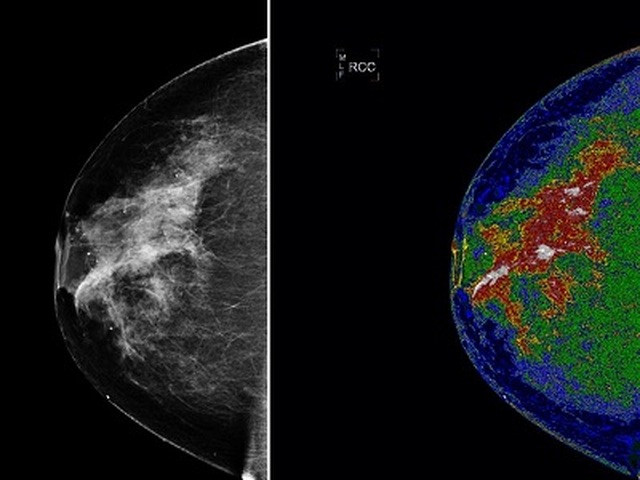

Bộ ngực dày

Vú dày đặc có nhiều mô liên kết hơn mô mỡ, đôi khi có thể khiến bạn khó nhìn thấy khối u trên chụp quang tuyến vú. Phụ nữ có bộ ngực dày dễ bị ung thư vú.